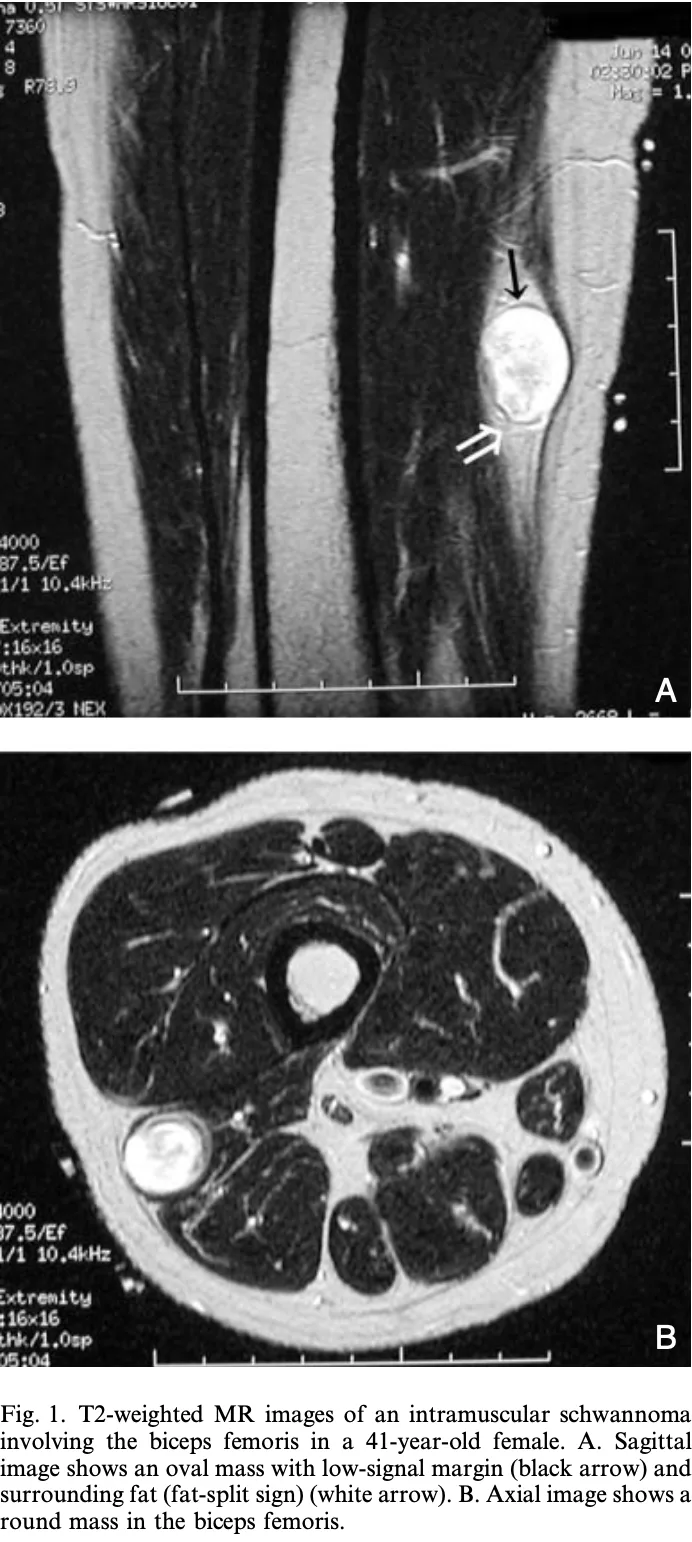

13時から, 下腿の筋肉内末梢神経性神経腫腫摘出術を執刀しました.

引用元:Shimose S. Major-nerve schwannomas versus intramuscular schwannomas. Acta Radio. 2007. 48.

筋肉内に発生する神経鞘腫は, 神経鞘腫の2 %程度とまれな病態で, 痛みがないのが特徴です.

主幹神経から発生する神経鞘腫のように, 手術によって麻痺を生じる危険性が少ないため, 局所麻酔で核出することにしました.